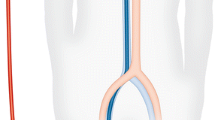

Right internal jugular Avalon cannulas are inserted 31 cm into the central vascular system using the Seldinger technique, percutaneously placed in the vessel using a guidewire and serial dilations under fluoroscopic and/or echocardiographic insertion guidance [18] (Fig. 1). The catheter traverses the superior vena cava, right atrium, with the tip placed in the inferior vena cava. Venous drainage ports positioned in the superior and inferior vena cava draw blood to supply the oxygenator. After gas exchange, the blood is returned to the infusion lumen of the catheter, terminating at a port directed toward the tricuspid valve that delivers a jet of arterialized blood to the right heart (Fig. 2). Insertion of the OriGen DLC is also percutaneous into the right IJ vein, but the tip of the cannula is inserted into the RA. Likewise, the 18 and 22 Fr. NovaPort twin DLCs are inserted 17 cm via the IJ vein into the RA. The largest NovaPort twin 24 Fr. DLC is inserted into the femoral vessel.